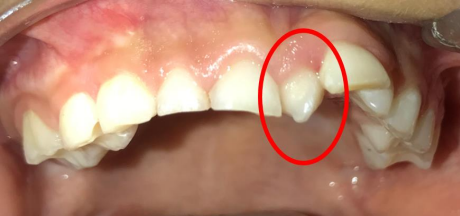

Es importante que los cirujanos dentistas, odontopediatras, médicos pediatras, e incluso los antropólogos, genetistas y otros profesionales de la salud conozcan la prevalencia de anomalías dentales en diferentes comunidades (6, 12). Se han realizado algunos estudios epidemiológicos y hay variaciones considerables entre sus hallazgos. Se ha discutido en la literatura que cuanto antes el diagnóstico mejor el pronóstico. El conocimiento del clínico sobre anomalías más comunes y su ubicación en la dentición primaria, mixta y permanente resultará en un diagnóstico precoz y, en consecuencia, puede prevenir complicaciones adicionales. El diagnóstico puede ser posible a partir de los 2 años y más según lo recomendado por algunos autores (6). Mediante la inspección clínica se pueden observar los mesiodens que han erupcionado en boca (figura 1); de igual forma, cuando existe un retraso en la erupción de los incisivos permanentes se puede intuir la presencia de un mesiodens. Por otro lado, a la palpación podemos obtener más datos clínicos que nos la situación del mesiodens por palatino o vestibular (30).